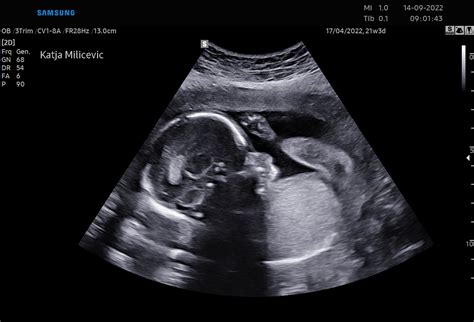

Ultrazvočni Pregled v 18. Tednu

Pregled za izključitev anomalij, znan tudi kot morfološki ultrazvok, vam običajno ponudijo med 18. in 20. tednom nosečnosti. To je standardna ultrazvočna preiskava, s katero se prepričajo, da je z vašim otrokom vse v redu. V preiskavi se podrobno pregleda otroka in ugotovi, ali je pri njegovem videzu in razvoju kaj nenavadnega. S tem pregledom je mogoče odkriti številne bolezni, vendar ne vseh. Večina pregledov pokaže zdrave otroke, če pa odkrijejo kaj nepričakovanega, vam bodo morda ponudili vrsto nadaljnjih testov.

Pri tem pregledu bo zdravnik morda lahko ugotovil tudi spol vašega otroka. Vendar pa je to podatek, ki ga ne želijo izvedeti vsi, in tudi bolnišnice imajo včasih pravilo, da se spola ne sme razkriti. Če želite izvedeti spol, se prepričajte, da se je plod postavil v ugoden položaj, saj lahko le tako izkušeni ginekolog točno določi spol.